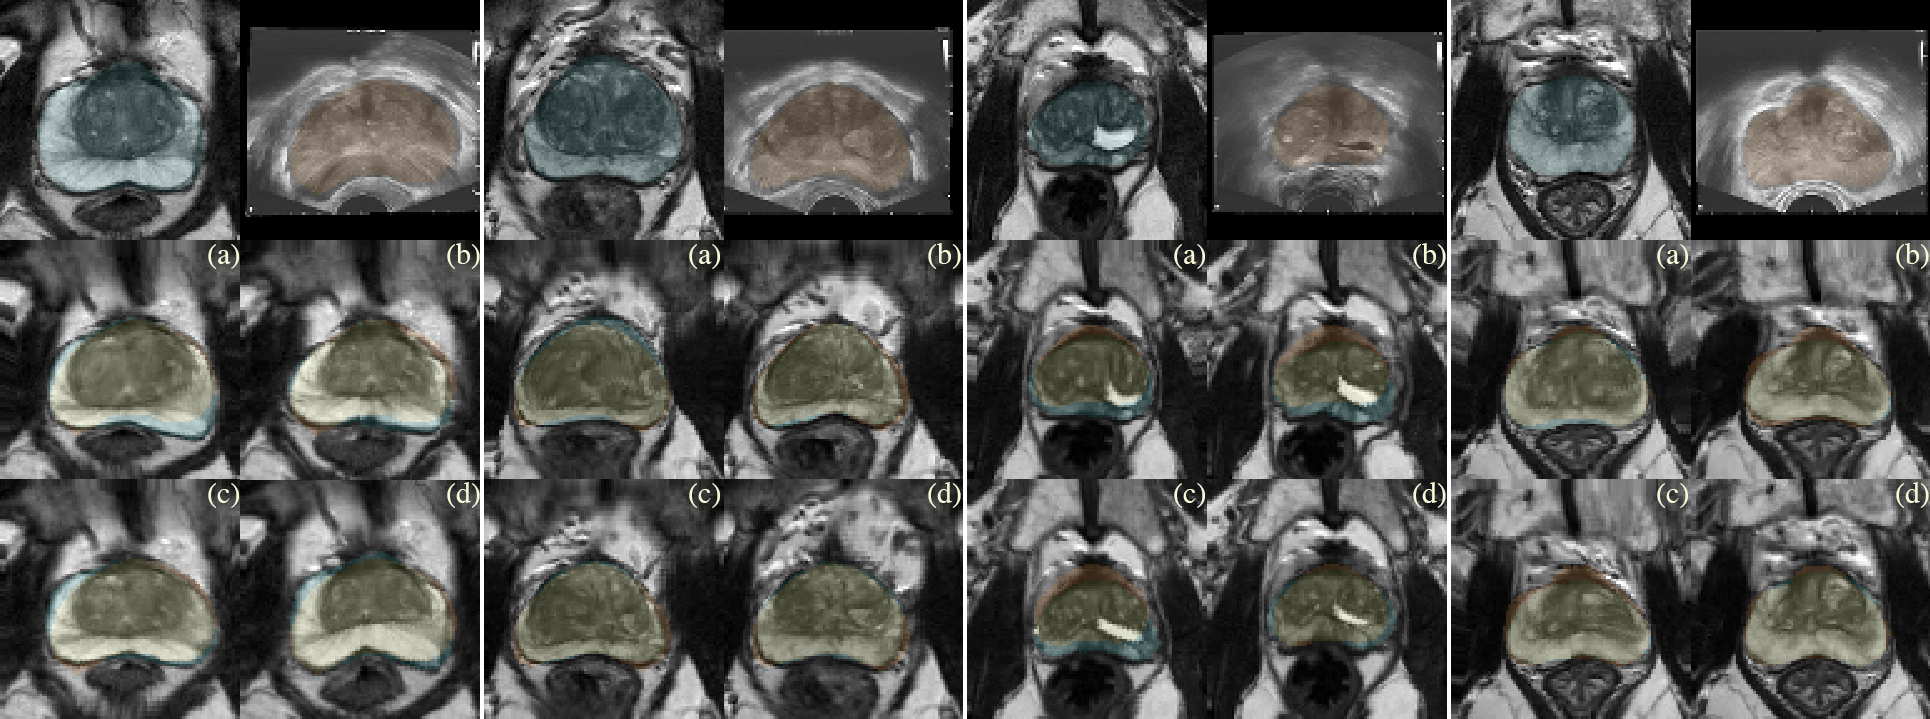

Fig. 3: Qualitative comparison of the proposed approaches: (a) multiscale Dice similarity coefficient (mDSC), (b) signed distance maps (SDM), (c) mixed strategy (MIX), and (d) its variation with mask (MIX+). Each 3×\times2 block depicts individual case. Top row contains pre-aligned MR-TRUS pairs. The slices were taken in axial plane with MR segmentation (cyan), TRUS segmentation (orange), and segmentation overlap (yellow).

Visual inspection revealed that mDSC-based models tend to stretch the inner organ structures to its boundaries, whereas the SDM-based models demonstrated a more uniform and natural deformation pattern (Fig. 3), also resulting in a better TRE score. However, the SDM model fails to produce smooth deformation according to the second-order smoothness measure |J|𝐽\nabla|J| (see Fig. 4). Since mDSC approach entails the regularization effect on the DDF, it is reasonable to try to combine it with SDM. The performance score of such approach indicates that MIX learning yields a much smoother transformation than SDMs while preserving the high registration accuracy.